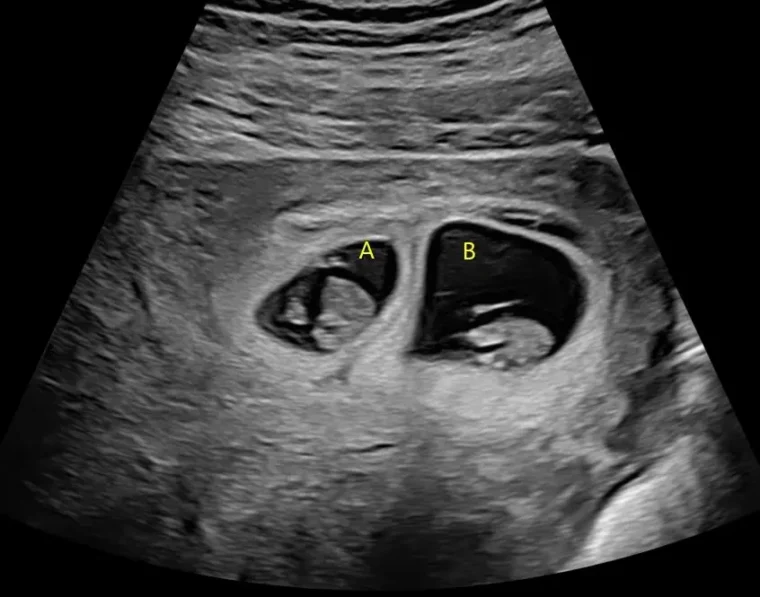

Whilst an early pregnancy ultrasound is not recommended for all pregnancies, we recognise it remains an important test for those with complications of early pregnancy, are unsure of their conception date, or just need extra support in these early days. It can help check the viability of your pregnancy, check the pregnancy is growing in the right place, and identify twins early.

A third trimester ultrasound is an ultrasound scan performed during the final stage of pregnancy, typically after 28 weeks. It is usually recommended when there is a medical reason to assess the baby’s wellbeing, growth, or position. Unlike the routine scans performed earlier in pregnancy, not everyone will need a third trimester ultrasound unless advised by their healthcare provider.

A third trimester ultrasound may be recommended if there are concerns such as reduced fetal movements, high or low levels of amniotic fluid, abnormal fundal height (the size of your belly), maternal medical conditions (like high blood pressure or diabetes), previous pregnancy complications, or if the baby is suspected to be too small or too large for gestational age.

The main purpose of a third trimester ultrasound is to check how your baby is growing and developing. It allows the sonographer to measure your baby’s size, monitor growth over time, and assess the amount of amniotic fluid around the baby. The position of the baby (whether head-down, breech, or transverse) and the location and appearance of the placenta are also checked. Blood flow in the umbilical cord and other vessels may be assessed using Doppler ultrasound if there are concerns about the baby’s growth or overall health.